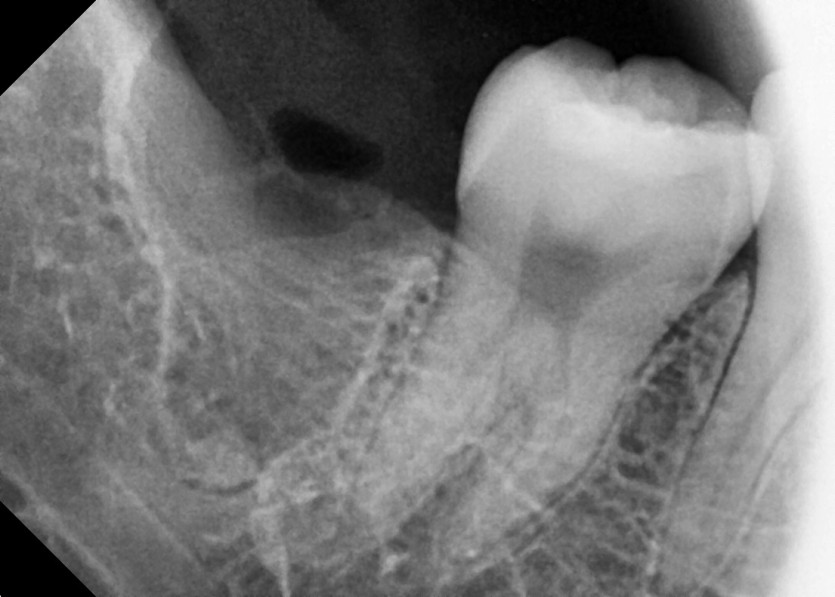

#38,48 사랑니 발치

구강 외과 전문의가 당일 발치했습니다.